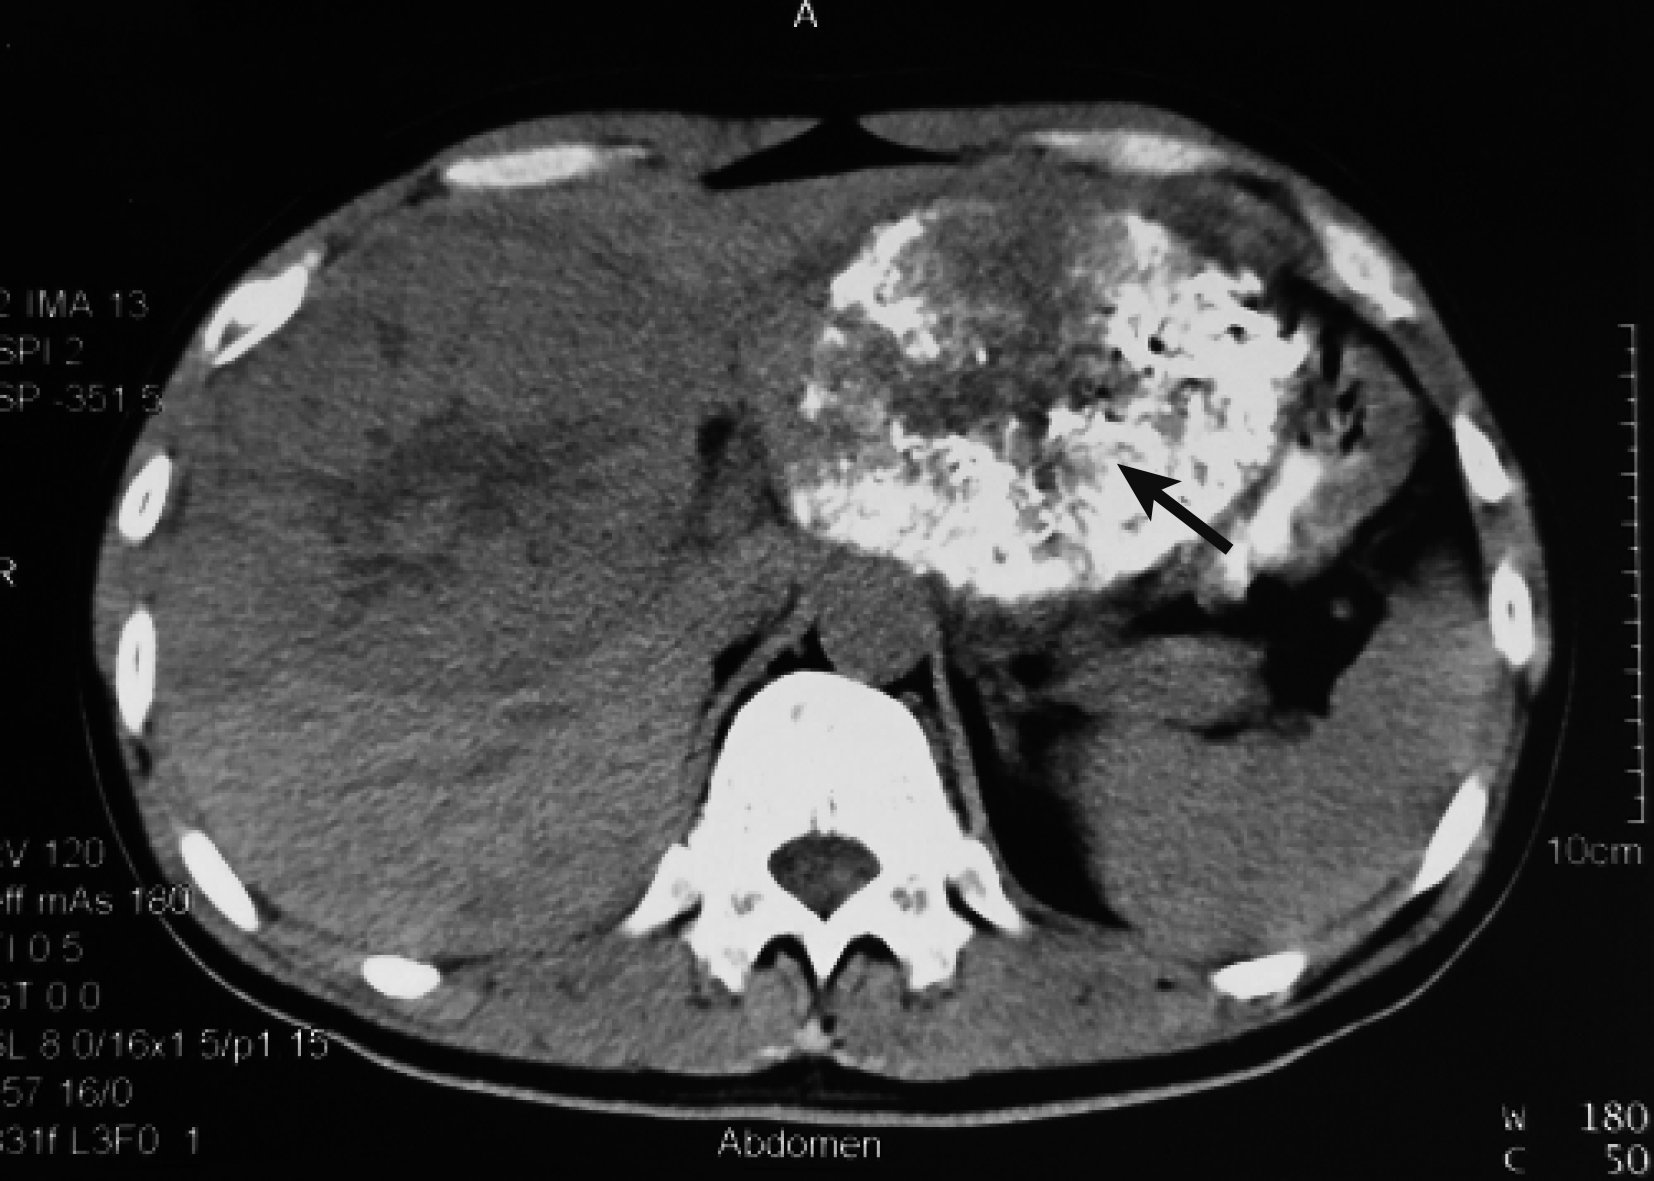

患者,男,37歲,初次就診時間2010-09-28;主訴劍突下脹痛 1+月由外院轉入筆者所在醫院。患者既往有慢性乙肝病史10+年,未規范治療及隨訪復查。否認丙肝、黑便、嘔血史。入院評估體質量指數(body mass index,BMI)為21.9 kg /m2,營養風險評分[4]為 1 分,日常生活能力(activities of daily living,ADL) 評級[5]為Ⅰ級,體力狀態評分參照美國東部腫瘤協作組(Eastern Cooperative Oncology Group score standard,ECOG)評分標準[6]評分為 0 分。查體示生命體征平穩,皮膚鞏膜無黃染,全身淺表淋巴結未觸及明顯腫大,心肺無特殊;右肋下及劍突下3 cm可觸及質硬腫物,不可推動。腹壁靜脈無怒張,脾臟未觸及。實驗室檢查:HBsAg(+),HBeAg(+),HBcAb(+),Pre-S1Ag(+);HBV-DNA 5.1E3 IU/mL;ALT 108 U/L,AST 112 U/L,PT、ALB及TBIL正常,肝功能分級為Child A級;吲哚菁綠試驗15 min滯留率(indocyanine green retention rate test for 15 minutes,ICGR15)為22.4%(日本光電DDG-3300K); 血清AFP>2 000 μg/L(化學發光分析法)。肝臟超聲造影檢查顯示:肝臟多發腫瘤性占位伴多發衛星灶。胸腹部增強CT(圖 1)顯示:雙肺正常;左肝及右肝前葉見多發占位,最大直徑約16 cm,呈典型快進快出表現,考慮HCC伴肝內轉移,門靜脈左支受侵犯。腫瘤體積/全肝體積為1 270 mL/2 209 mL=57.4%。